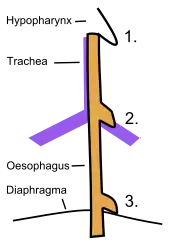

- Esophageal diverticula may occur in one of three areas of the esophagus:

- Pharyngeal (Zenker's) diverticula usually occur in the elderly, through Killian's triangle between the thyropharyngeus and cricopharyngeus muscle of the inferior pharyngeal constrictors.

- Midesophageal diverticula

- Epiphrenic diverticula are due to dysfunction of the lower esophageal sphincter, as in achalasia.[5]

- A Killian-Jamieson diverticulum is very similar to a pharyngeal esophageal diverticulum, differing in the fact that the pouching is between the oblique and transverse fibers of the cricopharyngeus muscle.[7]

- A Laimer diverticulum is an outpouching that occurs in the Laimer triangle between the cricopharyngeus and superior esophageal circular muscle.